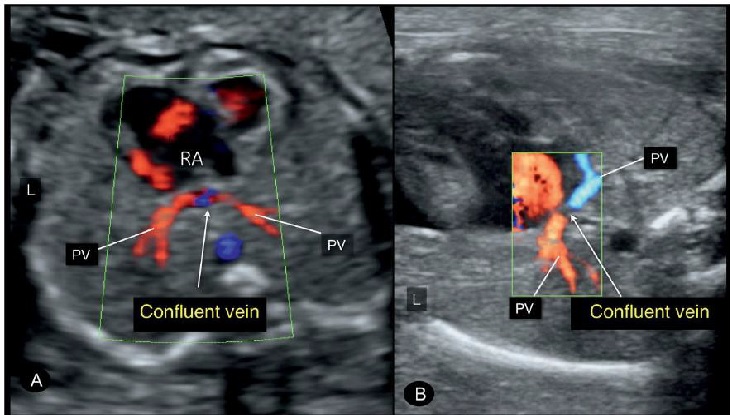

Hình 5: Hình ảnh mặt cắt ngang ngực 4 buồng tim, Doppler màu ở hai thai (A) và (B) đều có TAPVR, mỏm tim bên phải (dextrocardia) và kiểu hình bên phải (right isomerism). Lưu ý sự có mặt của các tĩnh mạch thu thập (confluent vein) phía sau tim. Doppler màu nên để ở thang vận tốc thích hợp và gain thấp để tách biệt rõ ràng giữa thành sau thất trái và tĩnh mạch thu thập (confluent vein).